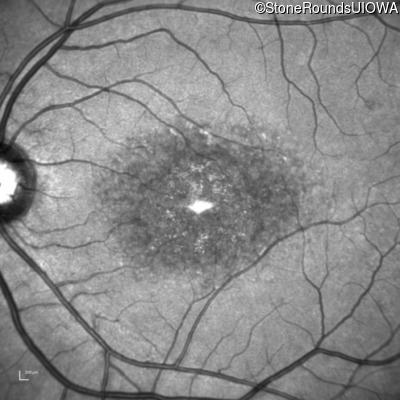

| Age at visit: 18 years |